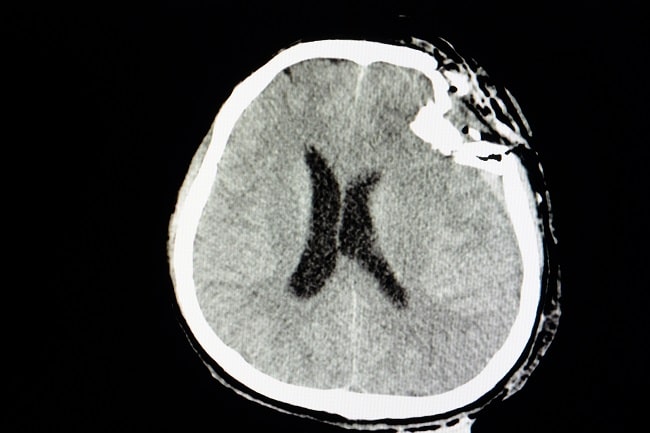

TBI merupakan kejadian yang sering ditemui dalam setting gawat darurat. Penilaian yang dilakukan untuk TBI hanya berdasarkan penilaian klinis hasil pemeriksaan radiologi seperti computed tomography scanning (CT Scan) dan magnetic resonance imaging (MRI).[1,4]

CT Scan kepala mempunyai sensitivitas yang rendah dan membuat pasien terpapar radiasi. Banyak pasien yang mengalami TBI menunjukkan penampilan anatomis yang normal pada pemeriksaan CT Scan. Sebaliknya, MRI otak mempunyai sensitivitas tinggi, tetapi merupakan pemeriksaan yang mahal dan ketersediaannya terbatas. Untuk itu, diperlukan pemeriksaan lain yang bisa digunakan untuk menilai TBI.[1,4]

Berbagai penelitian menunjukkan adanya korelasi antara peningkatan kadar S100β dalam darah dengan abnormalitas hasil pemeriksaan CT Scan otak. Pemeriksaan S100β dapat menurunkan kebutuhan CT Scan otak hingga 30%, dengan sensitivitas dan negative predictive value yang mendekati 100%.[6–8]

Kadar serum GFAP berhubungan dengan abnormalitas CT scan pada pasien dengan TBI, terutama jika dinilai pada 12 jam pascatrauma. GFAP juga diketahui berhubungan dengan diagnosis MRI untuk cedera aksonal sampai 3 bulan setelah cedera. Selain itu, pengukuran GFAP jangka panjang berkorelasi dengan pemulihan dari TBI sedang.[11]

Akson bertugas menyalurkan impuls dari badan sel ke neuron berikutnya. Tingkat keparahan kerusakan aksonal sering kali tidak sesuai dengan hasil temuan klinis. Kerusakan aksonal berat dengan kondisi klinis yang parah, seperti kondisi vegetatif persisten, dapat memiliki temuan CT scan yang minimal. Untuk itu, biomarker bermanfaat untuk membantu dokter menentukan diagnosis dan prognosis pada cedera aksonal difus (diffuse axonal injury).[11]